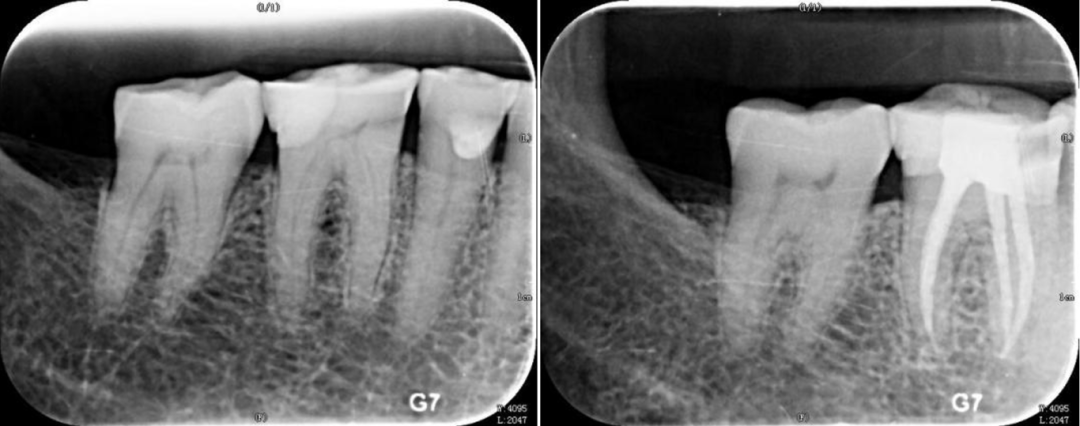

根尖片就是医生常说的小牙片,主要拍摄单颗牙齿,用来了解牙齿龋坏程度、根尖病变情况、牙齿周围支持组织及临近解剖结构,特别是对识别肉眼无法看到的邻面龋坏有非常重要的意义。

一般在做根管治疗前后,医生都会让患者去拍片,治疗前确定患牙龋坏范围、牙根情况;根管治疗结束后,拍摄根尖片确定填充效果,一般来说填充物会有一个非常致密的影像,且填充物距离根尖孔0.5~2 mm的距离为恰填,以后再次疼痛的概率会很低,此时也就可以放心去做牙冠修复了。